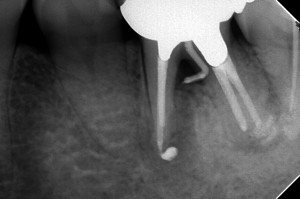

終了から7カ月経過

骨の平坦化が起きています。

これは何かというと、歯根の距離がそこそこ稼げていたために、

ここが平らになったのです。

炎症傾向もみられず、とても順調。